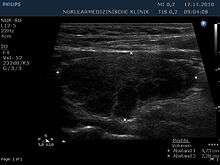

Ultrasound imaging of the thyroid gland (right lobe longitudinal) in a person with Hashimoto thyroiditis.

Diagnosis is usually made by detecting elevated levels of anti-thyroid peroxidase antibodies (TPOAb) in the serum, but seronegative (without circulating autoantibodies) thyroiditis is also possible.[18]